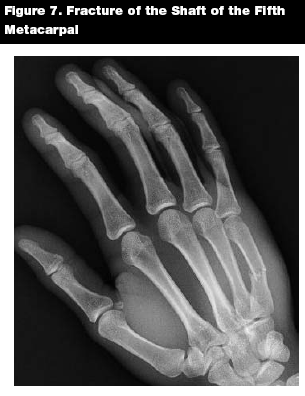

Fractures of the metacarpal shaft may be treated in a closed fashion with an appropriate splint. (See Figure 7) Very little angulation can be tolerated in the first two fingers. The ring finger can tolerate 20° of angulation, while the small finger can tolerate 30° of angulation.14,22

![]() |